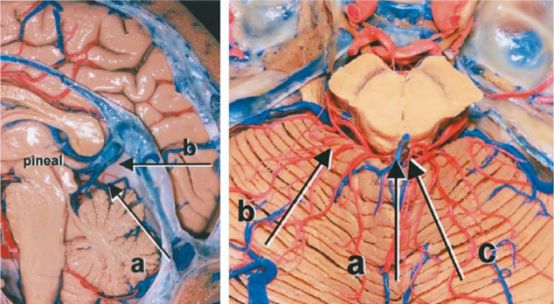

图5. 本图总结了松果体区的几种典型的手术入路。左图a所示为幕下小脑上入路,b所示为枕部经天幕入路;右图a所示为最常用的幕下小脑上中线入路,而笔者更青睐于b所示的旁正中入路,c所示为枕部经天幕入路(图片来自AL Rhoton,Jr)。